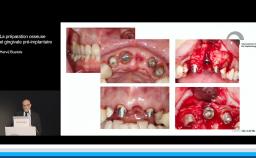

Cette présentation s’intéresse à l’influence des étapes chirurgicales sur le résultat esthétique en implantologie.

Il est communément admis qu’une épaisseur minimale de gencive kératinisée autour des implants est favorable au résultat esthétique mais aussi au maintien d’une bonne santé des tissus péri-implantaires au long terme, mais il n’existe pas de consensus à ce niveau. Une épaisseur osseuse de 2 mm autour des implants est nécessaire pour prévenir les résorptions osseuses et pour soutenir de façon pérenne les tissus mous.

- d’identifier les situations où une étape d’augmentation des tissus mous et/ou des tissus durs est nécessaire avant la mise en place de l’implant pour obtenir un résultat esthétique pérenne